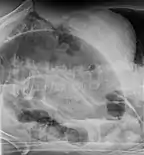

Diagnosis

After taking a thorough history, the diagnosis of colonic volvulus is usually easily included in the differential diagnosis. Abdominal plain x-rays are commonly confirmatory for a volvulus, especially if a "bent inner tube" sign or a "coffee bean" sign are seen. These refer to the shape of the air-filled closed loop of colon which forms the volvulus. Should the diagnosis be in doubt, a barium enema may be used to demonstrate a "bird's beak" at the point where the segment of proximal bowel and distal bowel rotate to form the volvulus.

This area shows an acute and sharp tapering and looks like a bird's beak. If a perforation is suspected, barium should not be used due to its potentially lethal effects when distributed throughout the free intraperitoneal cavity. Gastrografin, which is safer, can be substituted for barium.